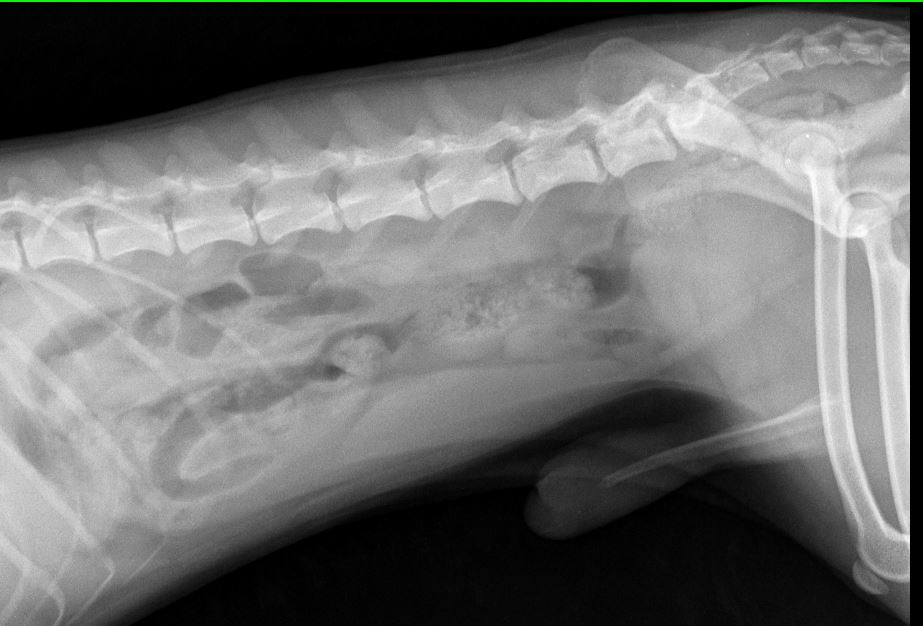

Прикладываю снимки, приблизила, чтобы лучше видно было. Также выкладываю снимок грудной клетки(этот снимок мы делали пару месяцев назад, когда он кашлял и врач исключал бронхит), на нем тоже есть ТБС, вдруг тоже на нем что-нибудь видно..

А где вы вывих тбс видите на снимках? И какой связки там нет?

В том то и дело, что я вывиха не вижу... Потому и сомневаюсь... пересмотрела наверное больше сотни разных снимков собак с вывихами, дисплазиями и другой ерундой, но на нашем снимке головка бедренной кости находится в вертлужной впадине, никаких наростов на ней нет, сама вертлужная впадина выглядит как глубокая чашка, а не как блюдце (которое описывают при дисплазии).. Потому и сомнения:(((

Если врач реально сказал то, что вы пишете - сходите к другому и проверьте колени (хотя по снимку и так видно)

По сабжу. Переделывайте рентген - собака лежит как черти что. Должна лежать прямо. Конечности должны быть строго параллельны, рентген ТБС делается с оттяжкой. Тогда можно будет говорить о корректных снимках (и только о них). О каких связках речь, если они на рентгене не видны? Для того, чтобы разглядеть связки вообще - делают КТ либо МРТ.

именно вывих, но коленной чашечки.

Даже при этой раскладке явно видно, что вывиха тбс нет.

Под наркозом и правильная раскладка важны при постановке дисплазии и Ее степени.